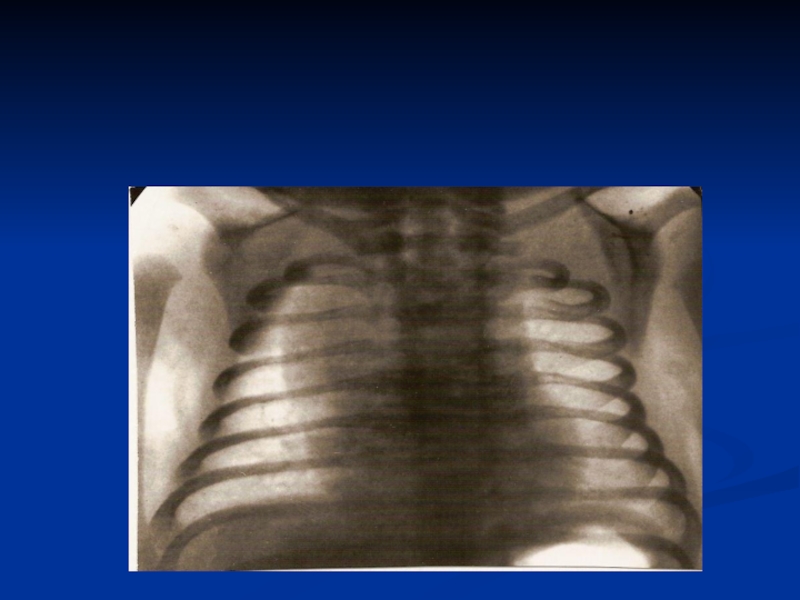

Слайд 45Оборудование

Рентегновские и УЗИ установки